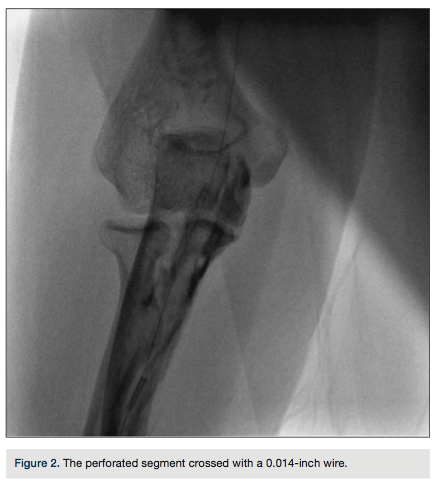

A 0.014-inch percutaneous transluminal coronary angioplasty wire was tactfully and carefully advanced through the area of perforation under fluoroscopic guidance (Figure 2). A diagnostic

catheter was inserted up to the proximal axillary artery over the wire (Figure 3). The wire was exchanged for a 0.035-inch, 260-cm long wire through the catheter. During left heart catheterization, this wire maintained position in the ascending aorta to exchange the catheters. The patient received 50 units/kg of unfractionated heparin during the procedure. Diagnostic coronary angiography demonstrated normal coronary arteries with mild luminal irregularities. The procedure was completed through the same RA access obtained at the beginning of the procedure. At the end of the left heart catheterization, the catheter was pulled

back over the wire just distal to the perforated segment, and a radial arteriogram was performed while slowly retracting the catheter (Figure 4).